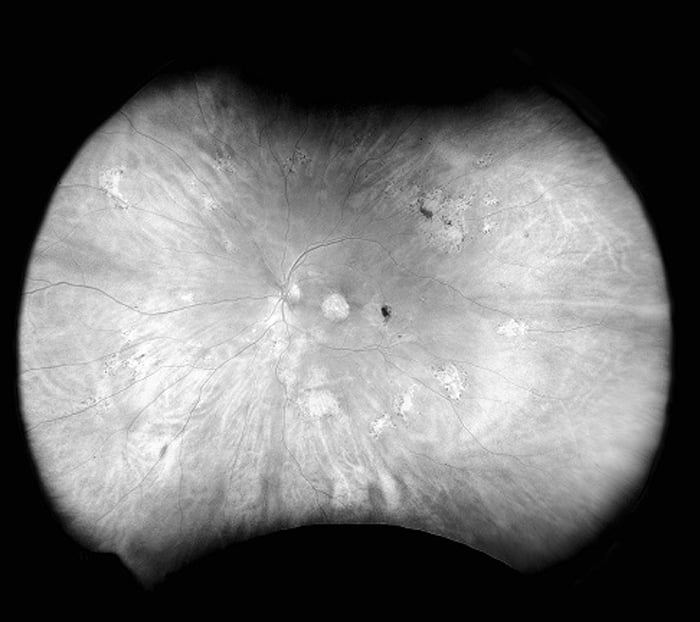

Daytona produces a 200° single shot optomap retinal image of unrivaled clarity in less than ½ second. This fast, easy, patient friendly, ultra-widefield imaging technology was designed for healthy eye screening and has been shown to improve practice flow and patient engagement.

Daytona provides eyecare professionals with UWF digital images of 200 degrees or up to 82% of the retina in a single, non-contact optomap image. In addition, the Daytona device comes with the OptosAdvance™ browser-based image review software, which allows for simple documentation, monitoring and referral processing to assist in patient management and improved patient flow.